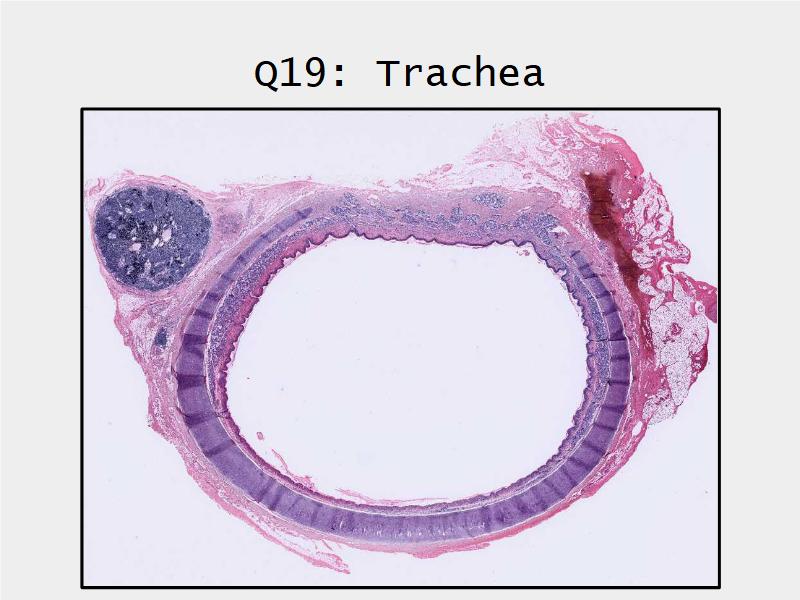

Respiratory Epithelium: Trachea

Today and Now I will do something for my future self.Trachea

- Slide 73: Trachea